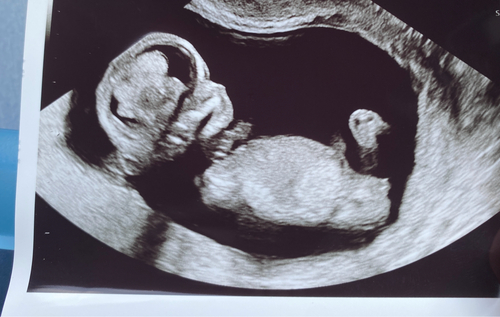

Een jongen! 馃挋 nub wijst flink omhoog.

Het bovenste streepje is denk ik de navelstreng en dat onderste streepje daar pas je de nubtheorie op toe. Dat onderste streepje wijkt wel iets af naar boven dus in deze zou je kunnen zeggen hey word een jongen. Bij een meisje schijnt hey echt horizontaal te liggen maargoed het is maar een theorie

Onder de navelstreng zie je inderdaad dat de nub naar boven wijst. Plaats je foto ook eens in het algemene nub theorie topic :) weet zeker dat je alleen 馃挋馃挋馃挋 krijgt 馃グ